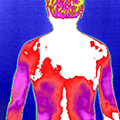

治疗前后炎症对比图/ Inflammation contrast

• 治疗前

• 治疗后